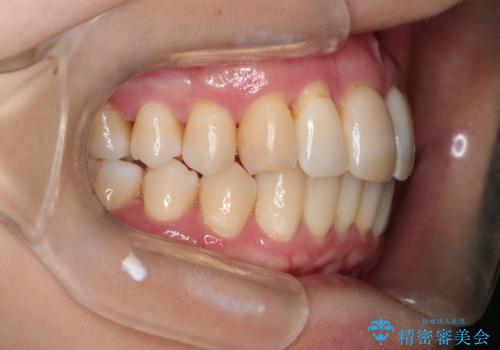

- 矯正装置

- インビザラインライト

- 治療期間

- 8ヶ月